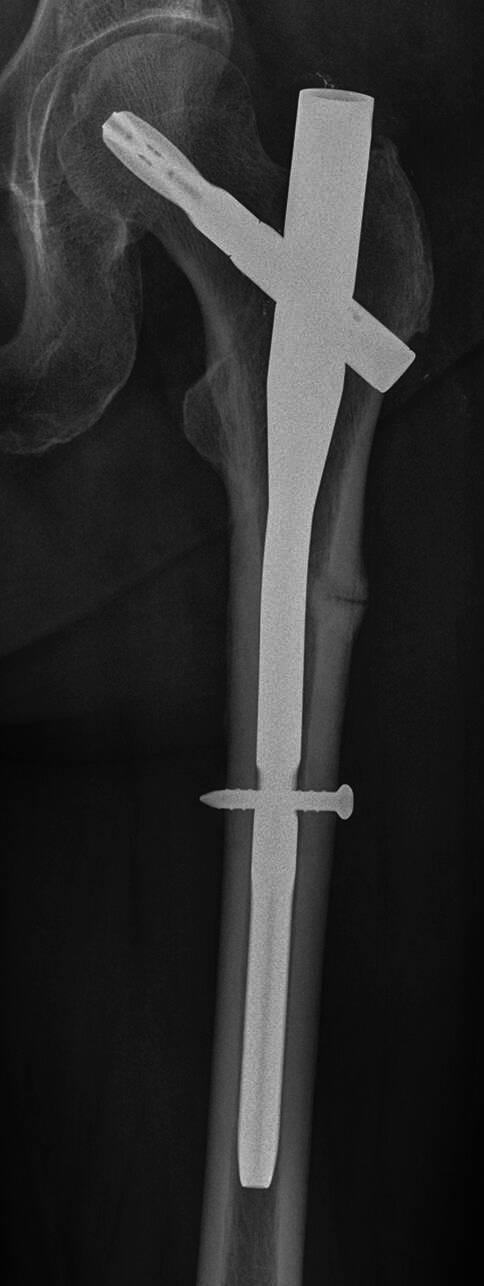

The guidelines include all aspects associated with osteoporosis and osteoporotic fractures, such as secondary causes, prevention, diagnosis, estimation of the 10-year fracture risk using FRAX®, determination of Austria-specific FRAX®-based intervention thresholds, drug-based and non-drug-based treatment options and treatment monitoring. Recommendations for the office-based setting and decision makers and institutions in the Austrian healthcare system consider structured care models and options for osteoporosis-specific screening.

该指南涵盖了与骨质疏松症和骨质疏松性骨折相关的所有方面,如继发原因、预防、诊断、使用FRAX®评估10年骨折风险、确定基于奥地利特定FRAX®的干预阈值、基于药物和非药物的治疗选择以及治疗监测。针对奥地利医疗保健系统中基于门诊的环境、决策者和机构的建议考虑了结构化护理模式和骨质疏松症特异性筛查的选项。